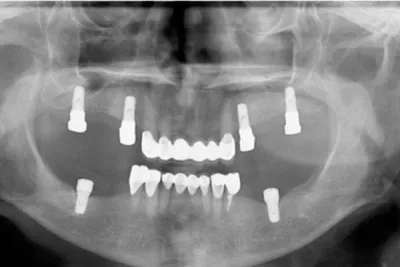

Цифровой рабочий процесс для создания окончательного гибридного протеза с опорой на имплантаты

Гибридные протезы с опорой на имплантаты стали популярным решением при лечении пациентов с не подлежащими восстановлению зубами или полным отсутствием зубов. С момента внедрения остеоинтегрируемых дентальных имплантатов для лечения потери зубов для изготовления несъемных гибридных протезов всего зубного ряда использовались различные ортопедические конструкции и материалы. Хотя такие реставрации могут быть весьма успешными, наиболее частые неудачи связаны с отсутствием места для протеза или с отсутствием пассивного прилегания каркаса, что может привести к сколам, расслоению и/или переломам. В данной статье рассматриваются клинические и лабораторные этапы изготовления окончательных гибридных протезов с опорой на имплантаты с применением шаблонов для снижения объема кости, шаблонов для создания ложа имплантата и немедленной фиксации временного протеза, изготовленного с использованием цифровых технологий.